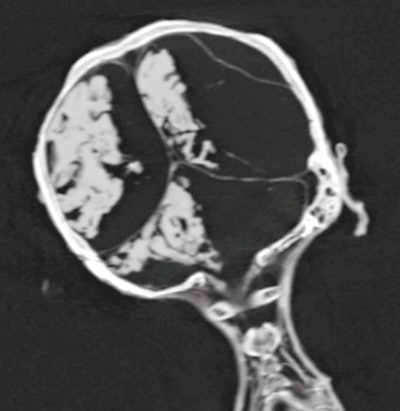

Coronal CT image of the head and neck of mummy shows the desiccated brain shifted to the right side of the cranial cavity.

3D CT image of the upper body of the mummy shows the gaping left inguinal evisceration incision. The disrupted anterior abdominal wall (likely inflicted by tomb robbers) reveals embalming material packs within the body cavity.3D CT images of the mummy documented the tilted head position, while 2D CT image showed intactness of the skull base, without any attempt of brain removal. The desiccated shrunken brain is seen in the CT images shifted to the right side of the cranial cavity. No resin or other embalming materials are seen within the cranial cavity.